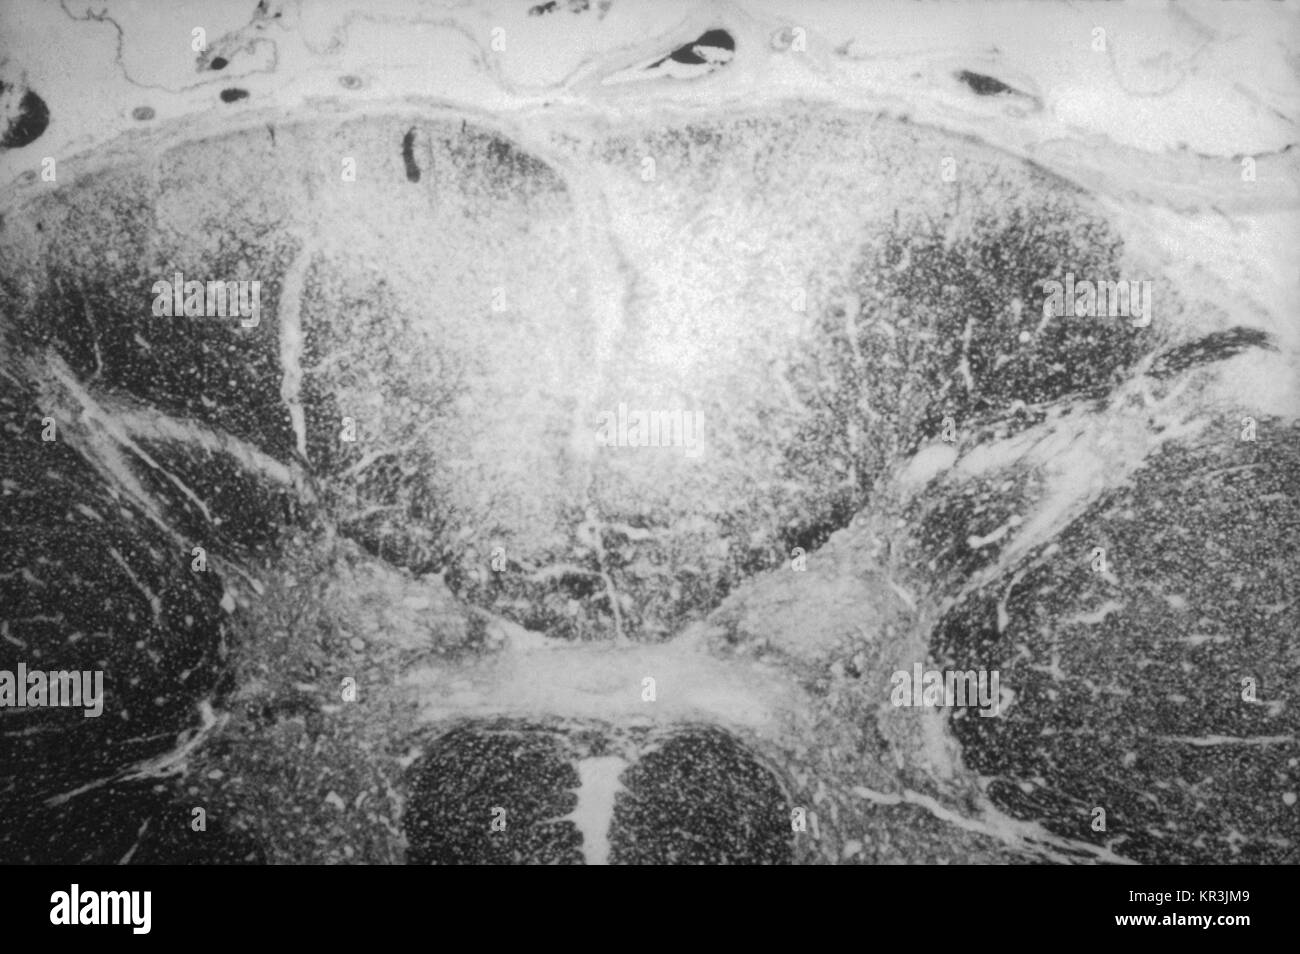

From www.alamy.com

Tabetic neurosyphilis hires stock photography and images Alamy Tabes Dorsalis Tabetic Gait Tabes dorsalis is a slowly progressive degenerative disorder of the dorsal column and dorsal root of the spinal cord. Syphilis is a sexually transmitted disease caused by treponema pallidum, with human beings as the only host. This gait can be seen in disorders of the dorsal columns (b12 deficiency or tabes dorsalis) or in diseases affecting the peripheral nerves. Tabes. Tabes Dorsalis Tabetic Gait.